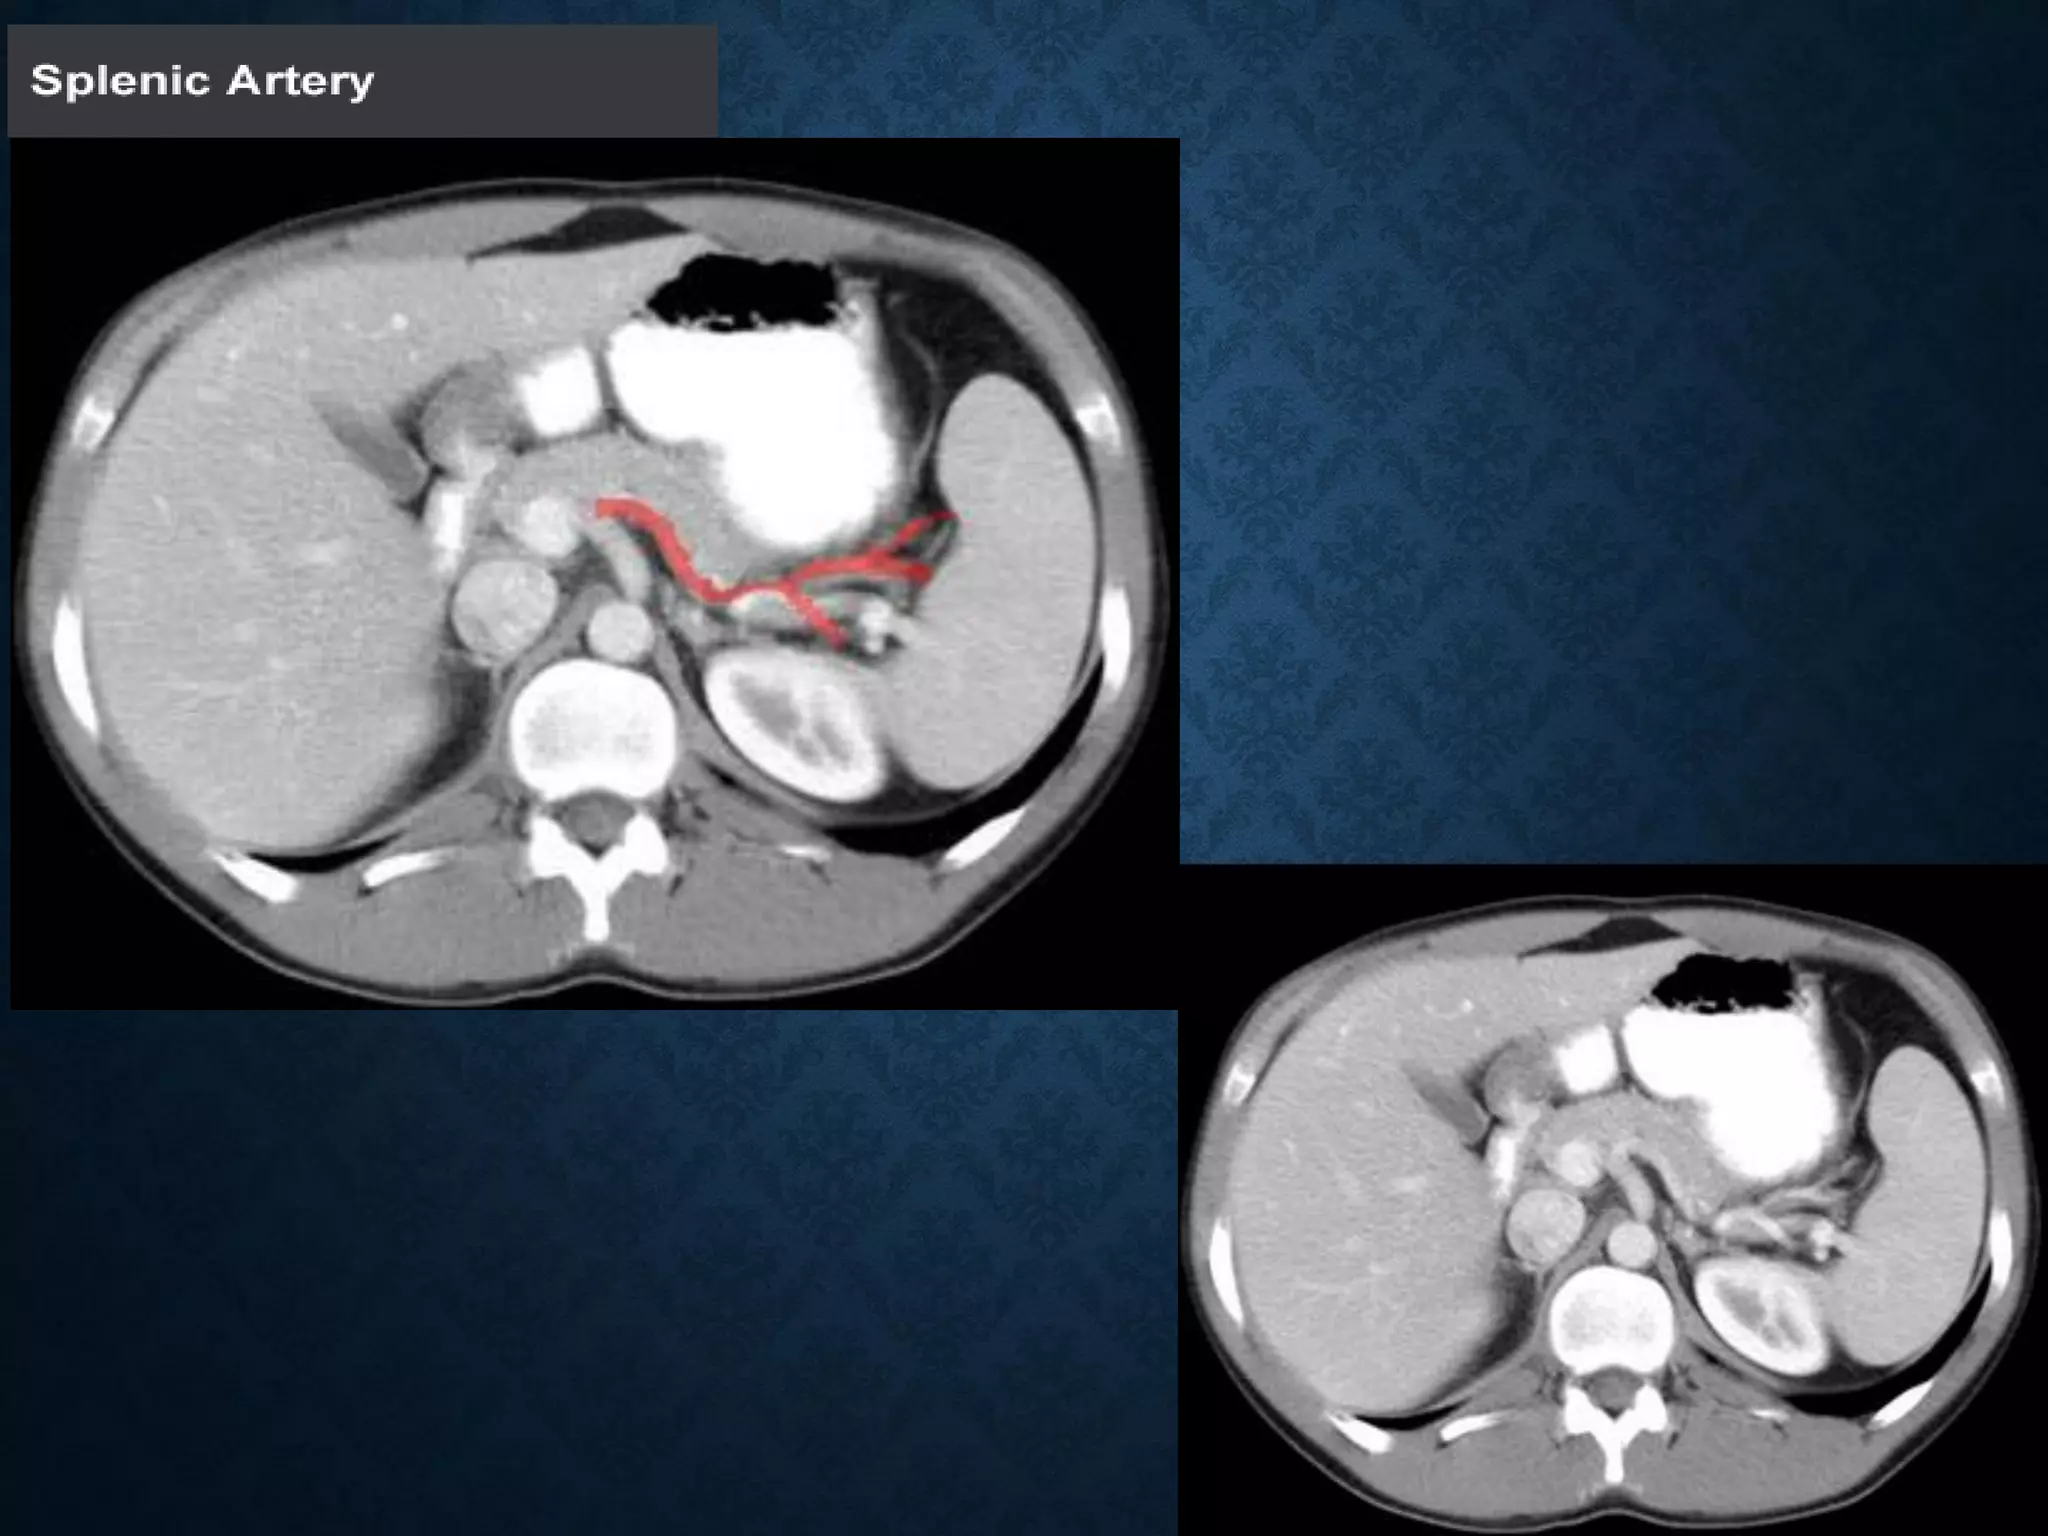

CELIAC ARTERY BRANCHES

• Left gastric artery

• Common hepatic artery

• Splenic artery

CELIAC ARTERY BRANCHES •Left gastric artery • Common hepatic artery • Splenic artery